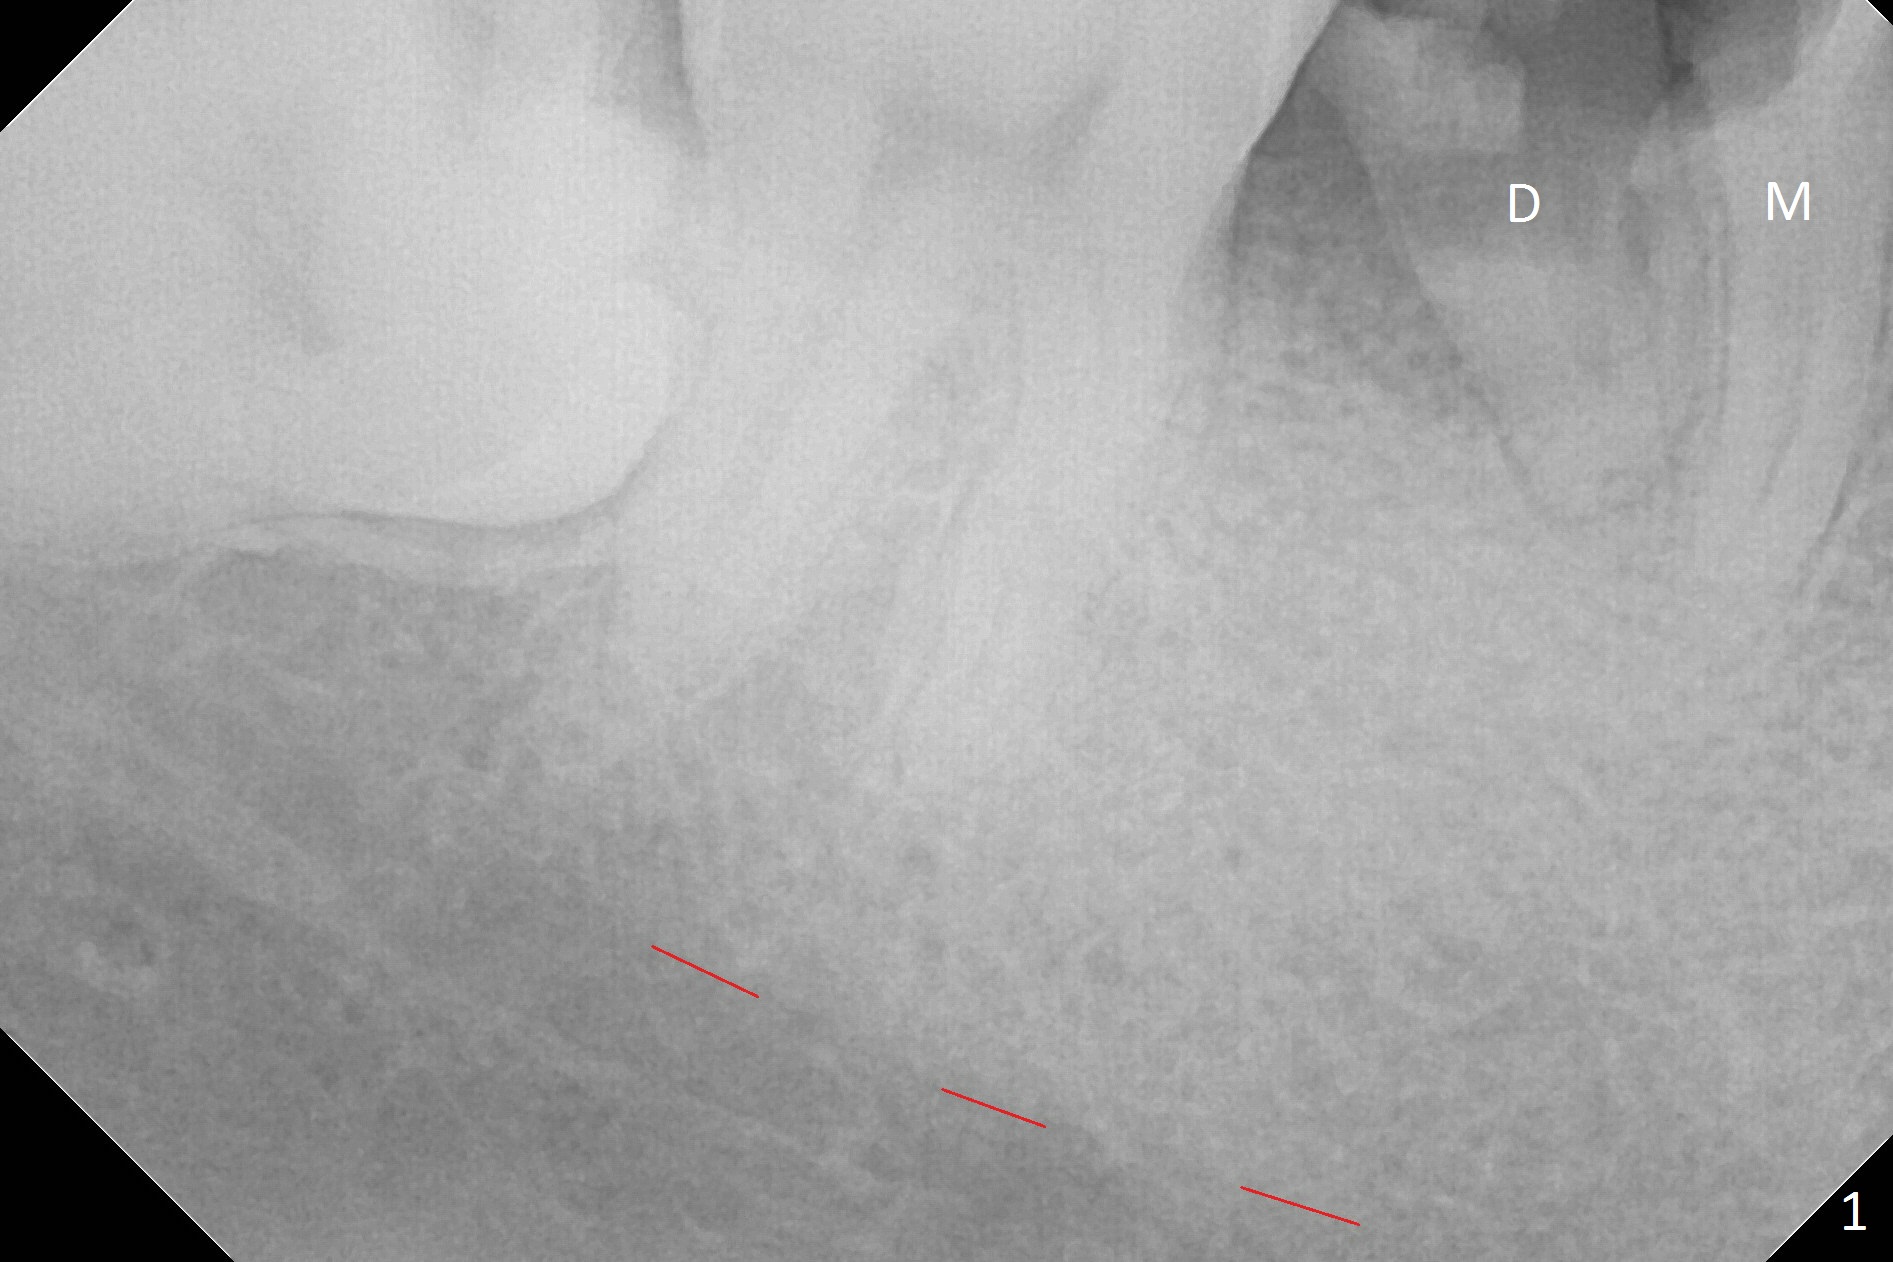

A 43-year-old man has residual roots at #30 (Fig.1). The mesial (M) and distal (D) roots approximates each other so close that the septum is thin (Fig.1,3-5). The latter is unfavorable for osteotomy. After extraction (Fig.5), the middle of the septum (Fig.8a (axial section of the sockets)) will be sectioned (Fig.6, 8b,c) prior to initial osteotomy (Fig.7,8d). The depth of the latter will be ~ 5 mm (Fig.2 red line) for a 13 mm (pink line) IBS implant.